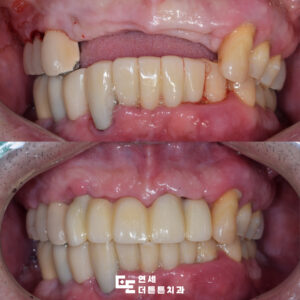

망월사역치과 변색된 아래 앞니 브릿지 수복

망월사역치과 변색된 아래 앞니 브릿지 수복 치아는 음식물을 씹고 끊는 저작기능 외에도 외모에 중요한 영향을 미치며 특히 앞니는 잘 드러나기 때문에 색상이나 배열이 좋지 않으면 타인에게 부정적인 인상을 줄 수 있습니다. ​ 이에 따라 보철치료가 필요할 때가 있는데 이를 고려하기 전에는 반드시 확인해야 할 중요한 사항들이 몇 가지 있습니다. ​ 더보기…